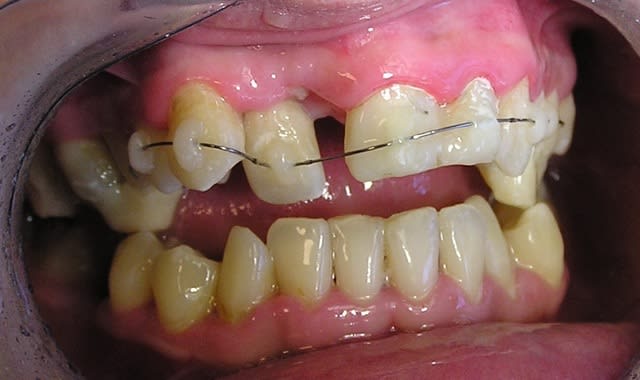

Après de nombreux échanges avec Dancha, j'ai mis en route ce cas.

On part de loin, on se bat encore pour l'hygiène mais on avance.

J'en profite pour renouveller un immense merci à Daniel pour le temps passé à transmettre ses connaissances (et il doit être colossal vu la précision de tes réponses).

arno